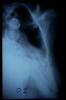

TBC pulmonar antigua